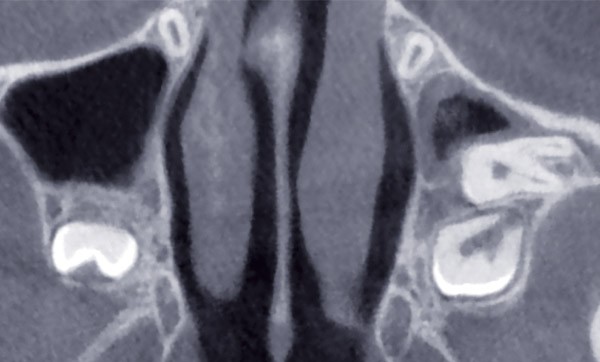

Le diagnostic positionnel de la dent incluse est également fondamental puisqu’il conditionne le plan de traitement orthodontique [2] ; il peut être déterminé au cours de l’examen clinique (inspection/palpation) et complété par des examens radiographiques conventionnels (orthopantomogramme [OPT], téléradiographie intrabuccale [TIB], téléradiographie de profil [TRG]) [3] ; l’apport de l’imagerie 3D (CBCT) présente de nos jours un intérêt majeur puisqu’il permet de localiser précisément la dent en 3D (angulation, rotation), de déterminer ses rapports avec les dents adjacentes et les éléments anatomiques de voisinage, de mettre en évidence une résorption ou une ankylose et d’évaluer la taille du sac péricoronaire.

De plus, cet examen 3D aide le chirurgien à déterminer la position de l’attache collée la plus favorable en fonction de l’orientation de la dent incluse et l’orthodontiste à envisager la direction de traction la plus appropriée.